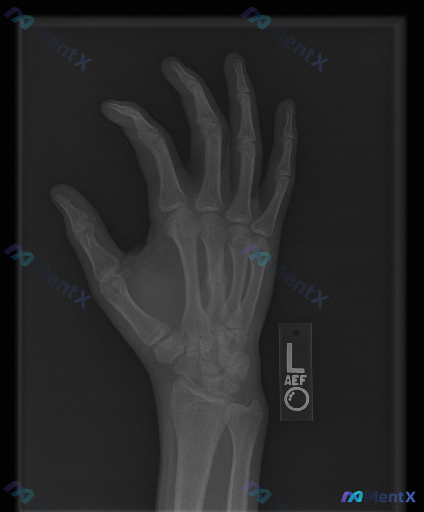

- 影像来源:左手正位X光片

- 常规阅片所见:

- 各腕骨、掌骨、指骨骨皮质轮廓尚完整,未见明显骨折线、脱位或半脱位;

- 骨密度、关节间隙未见明显异常;

- 关节面、软骨下骨、软组织影也未见明确的典型异常改变(如骨赘、弥漫肿胀、钙化/异物、明显骨膜反应等);

- 类风湿、退变、占位等特征性表现也未看到。

- 背景提示:存在异常。

也就是说,常规报告可能会写「本次影像学检查未见明显骨性结构异常」,但另一方面又明确提示有异常需要关注。